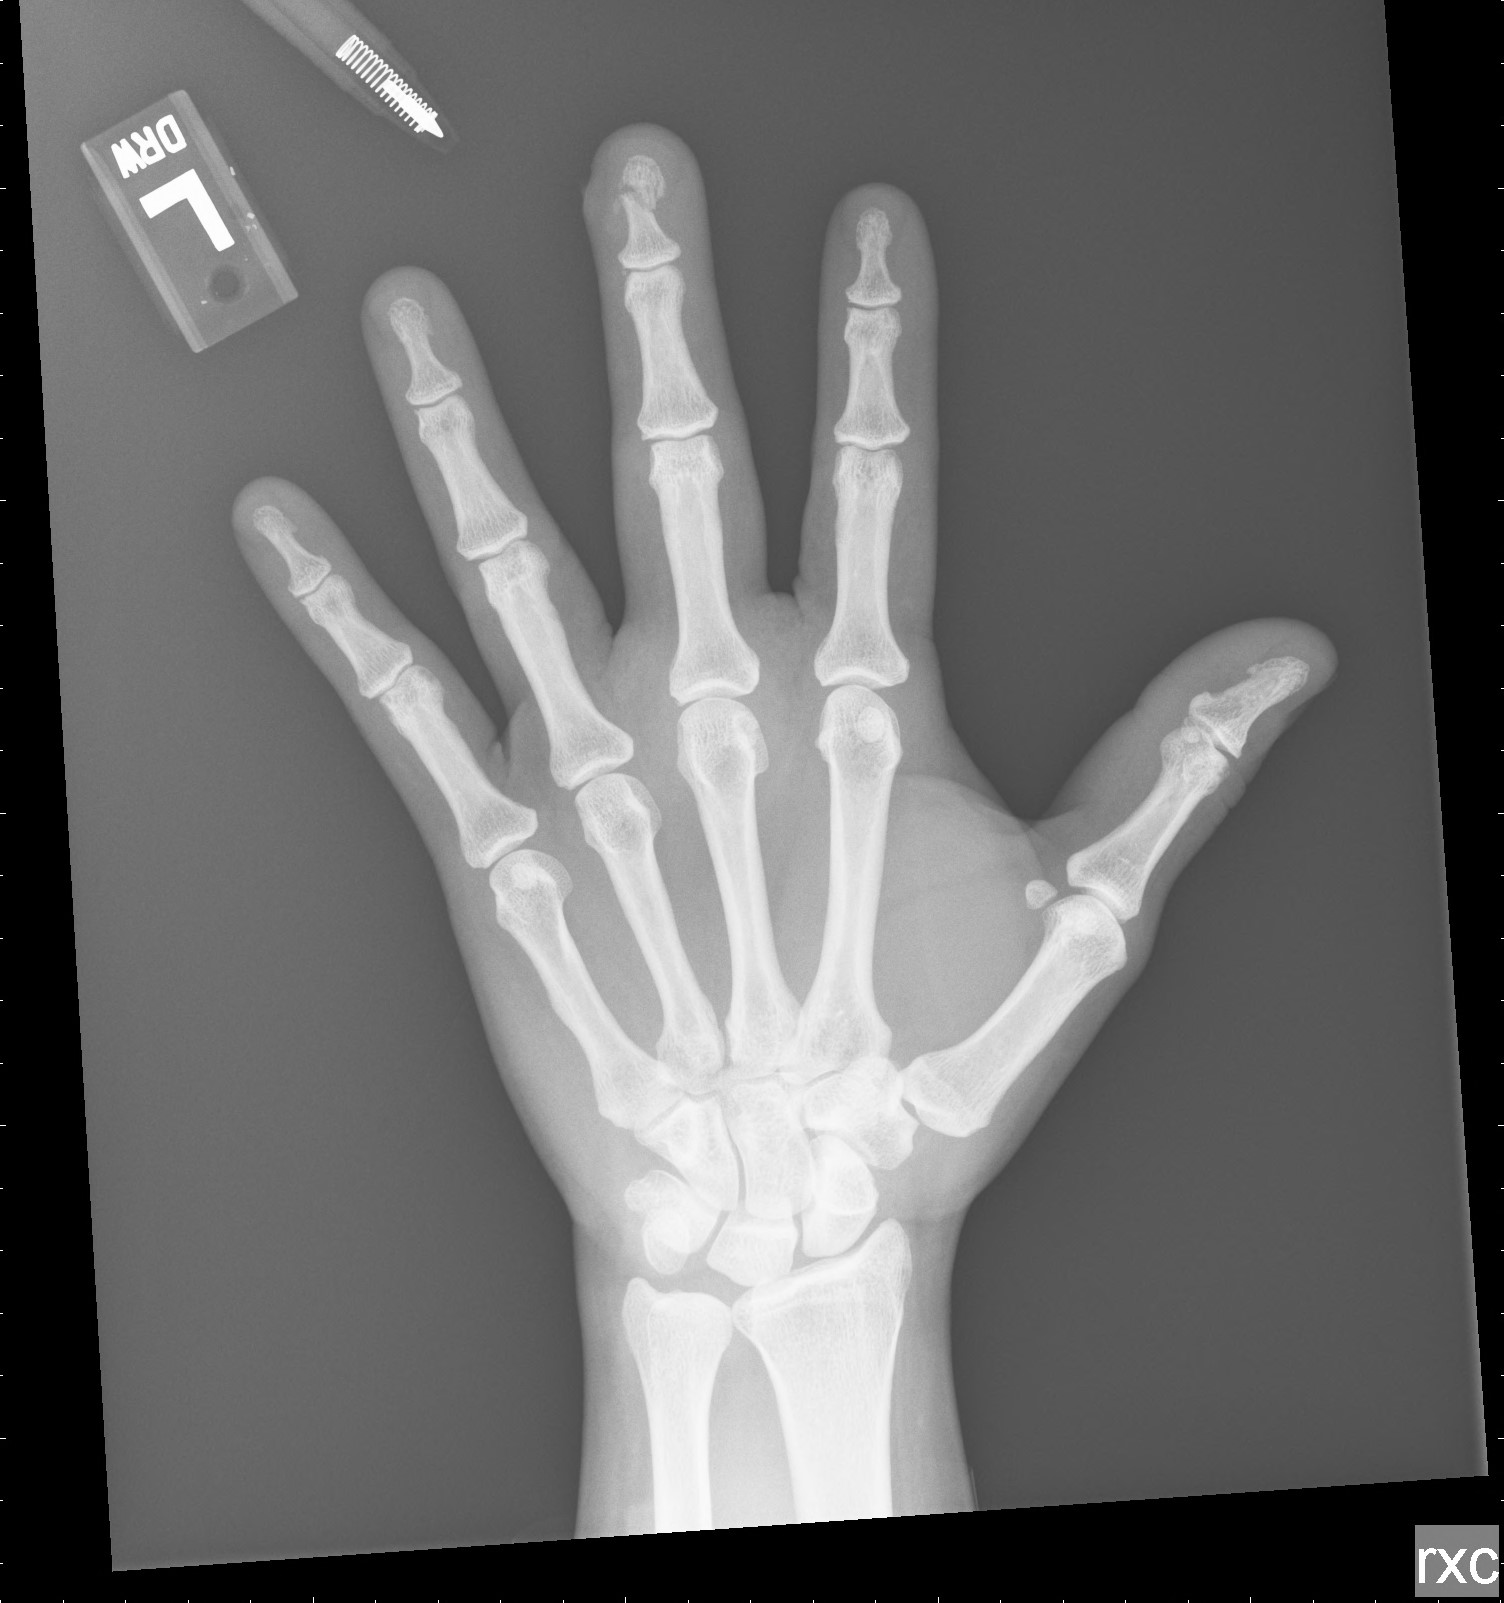

A 19 year old patient (they/them/theirs) was in a rush and slammed their finger in the car door on the way to work. Now, they are making a detour to your ER with this injury:

An X-ray is performed and reveals that this is not just a laceration–this is an open fracture of the distal phalanx. You recognize the immediate danger an open fracture represents for the patient and get on a call with your friendly neighborhood orthopedic surgeon to describe the injury.

- Let’s start with some precision. Not every fracture of the distal phalanx is the same, and only a small portion of the distal phalanx comprises the tuft.

- The proximal and middle phalanges of the hand all possess a head, neck, shaft, and base. In contrast, rather than a head and neck, the distal phalanx starts proximally with a base, then the next part is the shaft, and the most distal portion of bone is the tuft.

- So when we talk about the tuft, we are really talking about the most distal portion of the finger. This is key to recognize because proximal injuries of the distal phalanx have other considerations–like mallet finger formation if the extensor tendon is disrupted, or joint penetration if the fracture is intra-articular.

- All this said, the tuft does happen to be the portion most likely to present to us with an open injury.